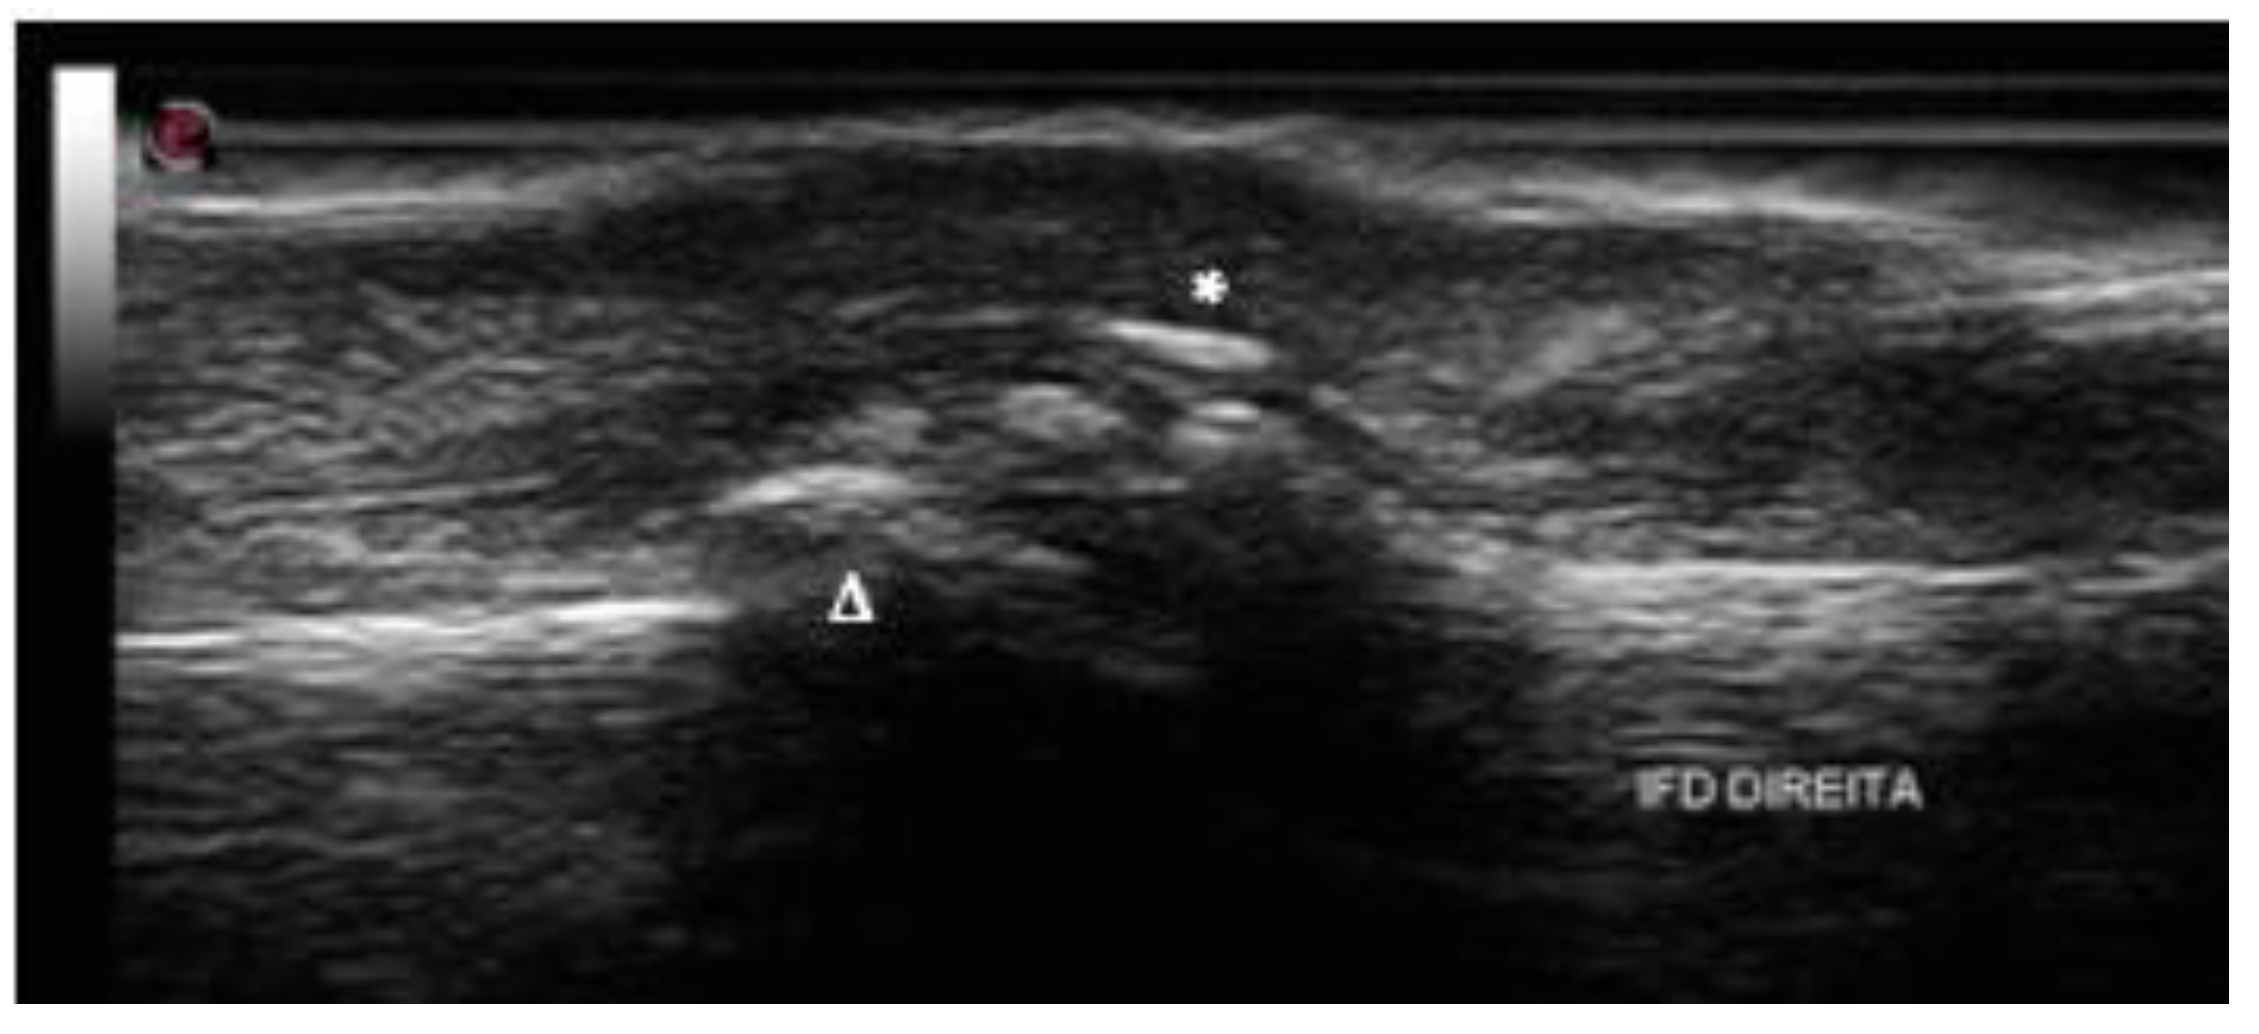

2.5. Dactylitis

- Tinazzi, I.; McGonagle, D.; Zabotti, A.; Chessa, D.; Marchetta, A.; Macchioni, P. Comprehensive evaluation of finger flexor tendon entheseal soft tissue and bone changes by ultrasound can differentiate psoriatic arthritis and rheu-matoid arthritis. Clin. Exp. Rheumatol. 2018, 36, 785–790. [Google Scholar]

- Tinazzi, I.; McGonagle, D.; Aydin, S.Z.; Chessa, D.; Marchetta, A.; Macchioni, P. “Deep Koebner” phenomenon of the flexor tendon-associated accessory pulleys as a novel factor in tenosynovitis and dactylitis in psoriatic arthritis. Ann. Rheum. Dis. 2018, 77, 922–925. [Google Scholar] [CrossRef] [PubMed]